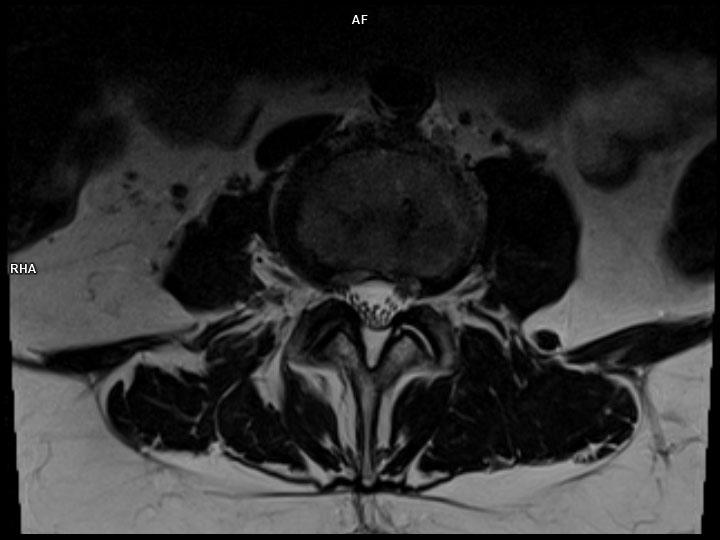

Axial T2 TSE-MAGNETOM Lumina

Axial T2 TSE-MAGNETOM Lumina/Coil-Spine 24/Resolution-368/Scan Time-3:52